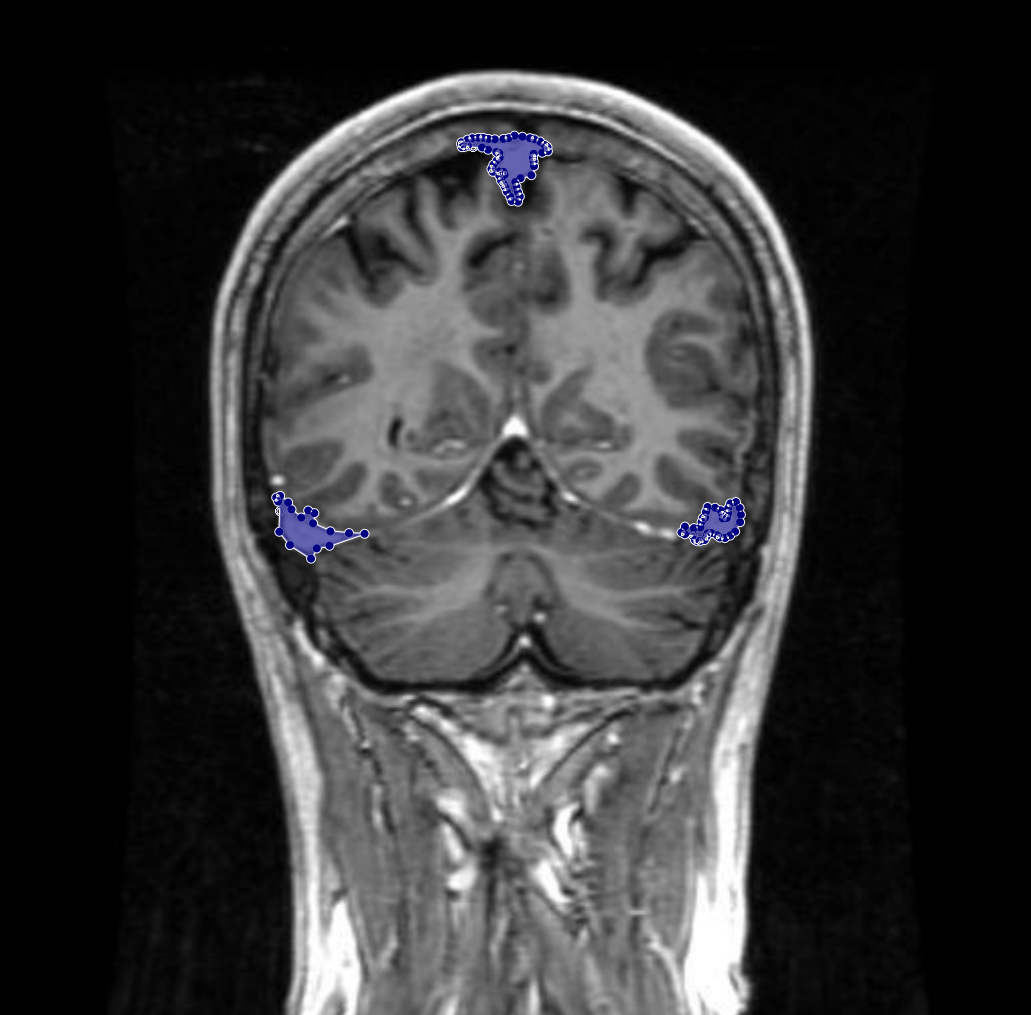

Figure 7: Samples of partial-region underannotations. The purple area indicates regions that were initially marked as non-tumorous but were later identified by the radiologist and physician as tumorous.

Conversely, there were cases where genuine tumor regions had been overlooked during the initial annotation process. With input from the Physician and radiologist, these missing regions were added to the annotations, ensuring that the masks comprehensively captured all tumor areas. Figure 7 demonstrates an example of such an adjustment, where previously unannotated tumor segments were correctly incorporated into the final mask.